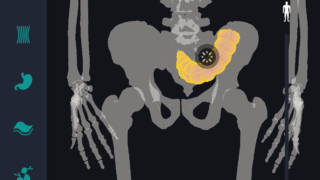

はじめに 本記事では、人体解剖学における専門的な部位の知識を始めに、効果的な勉強法についてご説明します。 人体解剖学では様々な器官や筋肉、骨の名称を覚えるだけではなく、体のどの位置に存在するのかまで覚えなければなりません。そのため、できるだ...